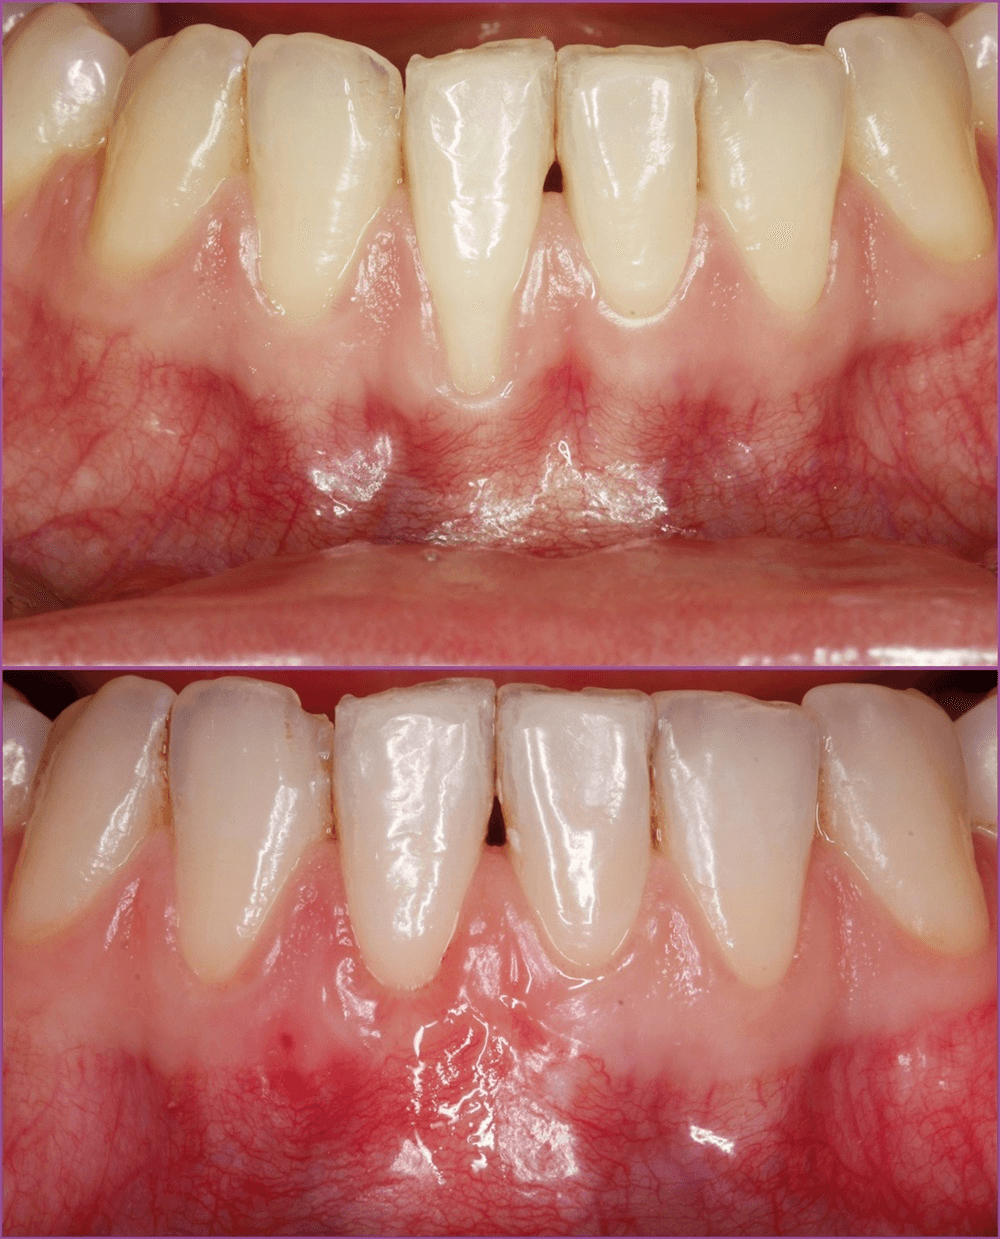

Az egyedüli valódi kezelés az ínyplasztika. Az ínyplasztika egy olyan beavatkozás, amely során visszaműtjük az ínyt a fognyakra. Bár az eredeti állapotot visszaállítani nem mindig lehetséges, komoly javulást tudunk elérni.

Az ínyplasztika sajnos nem mindenható, és nem minden helyzetben lehet alkalmazni. A fogak közötti ínyszövet visszaállítására például nem alkalmas. A fogorvostudomány sajnos még nem tart ott, hogy a fogak körüli csontpusztulás miatt kialakulú, nagymértékű fogínyrecessziót kezelje, ezelben az esetekben nem tudjuk “visszanöveszteni” a fogínyt.